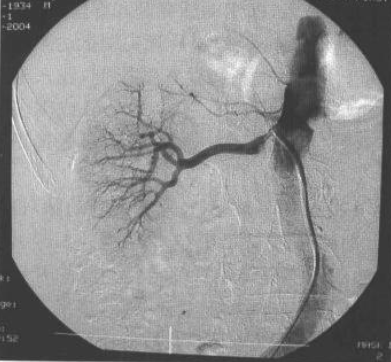

肾血管造影则是用来观察肾动脉或肾静脉的情况(图2),是一种对患者有一定危险性的有创检查方法。

图片

图2 腹主动脉-肾动脉造影像